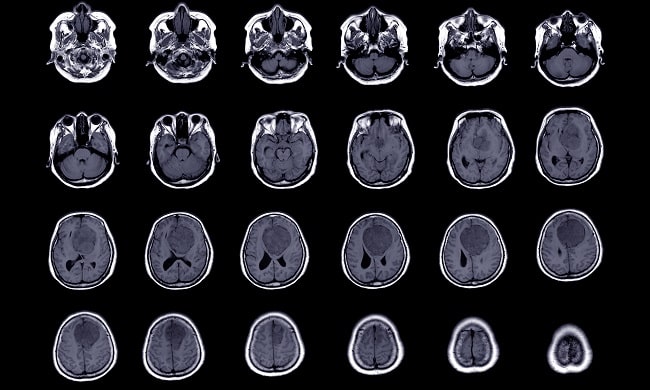

Pencitraan dengan magnetic resonance imaging (MRI) sering dilakukan untuk diagnosis meningioma. MRI pada T2 weighted image (T2-WI) yang menunjukkan gambaran hiperintensitas dan edema peritumor berhubungan dengan peningkatan laju pertumbuhan meningioma yang lebih cepat dan tingkatan meningioma menurut WHO yang lebih tinggi. Sebaliknya, gambaran kalsifikasi menunjukkan deselerasi pertumbuhan tumor. Pemeriksaan MRI tidak menggunakan radiasi sehingga aman untuk dilakukan secara berkala.[1,2]

Studi meta-analisis menyatakan adanya gambaran edema peritumor dan meningioma dengan volume >10 cm3 pada saat diagnosis merupakan prediktor perkembangan gejala. Studi mengenai hypointensity of tumor surface layer (HSL) pada MRI menunjukkan bahwa tumor dengan HSL berukuran lebih kecil dan lebih sering mengalami kalsifikasi.[1,2]

Temuan MRI berupa hiperintensitas pada MRI T2-WI, volume >10 cm3 dan edema peritumoral menunjukkan meningioma yang berisiko tinggi. Pada pasien yang berisiko tinggi tersebut, dapat dipertimbangkan intervensi dini berupa pembedahan atau radioterapi stereotaktik.